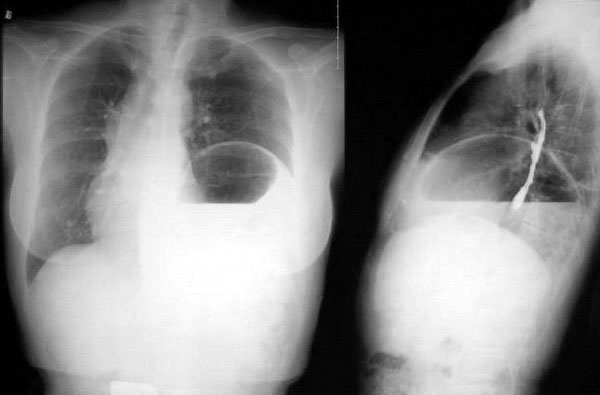

第三张04年

考虑隔疝

按楼主给出的片子时间,顺序说明病变有可恢复性及复发性,也只有左膈疝了,并且是可复性疝。

左侧隔疝.

典型左侧可复性隔疝

左侧膈疝没问题,不足之处在于食道吞钡后没有卧位片,看来经验少了点.

本例的诊断各位已经很肯定了---左侧膈疝。

膈肌有七个薄弱点:主动脉裂孔、下腔静脉裂孔、食道裂孔,及双侧对称的腰肋三角、胸肋三角。

膈疝常见于食道裂孔、胸肋三角、腰肋三角。

如果膈肌发育异常或后天外伤后破裂,可直接形成膈疝。

本例疝出的胃结构较大、较多,考虑为膈肌发育异常可能性大。经生理裂孔可能性小。

食道吞钡做得不完善,应该使胃部显影并加照卧位,找出疝环。

有没有可复性很难说,以前可复并不等于现在也可复,所以还是不要轻易下可复性疝。